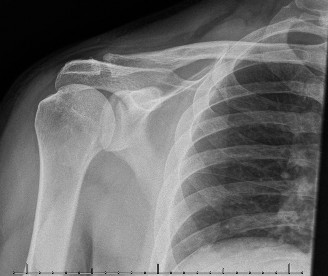

A 56-year-old male presents to your clinic 2 months after a polytrauma MVA. He was in the ICU, intubated for …